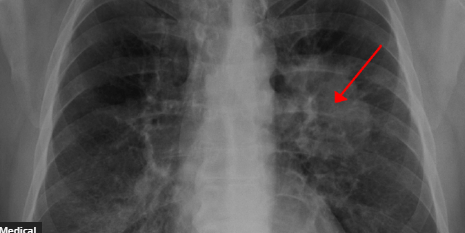

Lung cancer is the third most common cancer type in the United States and the world’s leading cause of cancer death. When the disease is discovered early on, it is frequently treatable. As a result, specialists are constantly developing new methods for early detection of lung cancer in order to provide people with prompt treatment.

The type of lung cancer and the stage at which it was discovered will determine the course of treatment. Radiation, surgery, immunotherapy, and chemotherapy are all treatment options. Dr. William Dahut, chief scientific officer of the American Cancer Society, clarified, “Lung cancer is by far the leading cause of cancer deaths in the U.S. Although the number of deaths per year is decreasing (due to decreased tobacco use, C.T. screening, and targeted therapies), it remains a very serious medical problem. Outcomes are much better if lung cancer is detected earlier.”